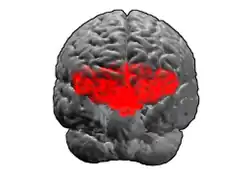

Image of brain with Brodmann area 11 shown in red | |

Animation.

Animation. -